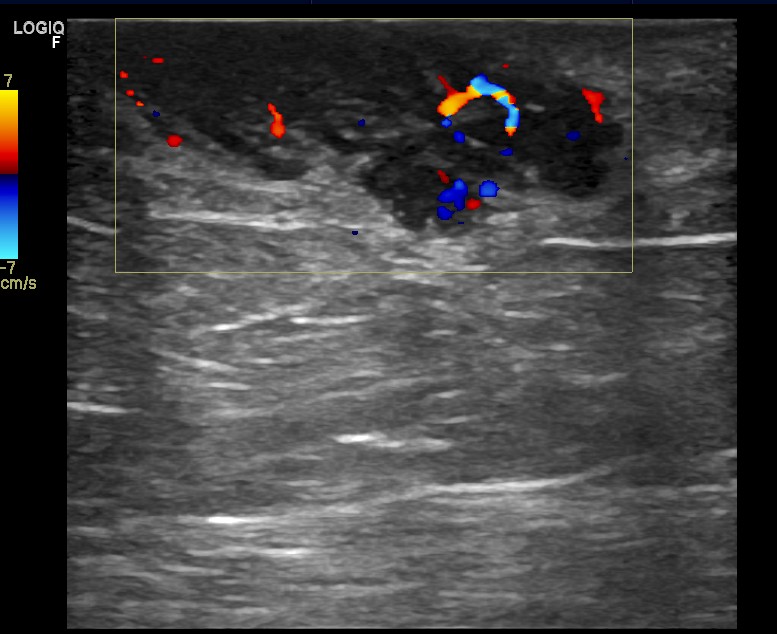

Hallazgos ecográficos

Tras ausencia de mejoría, realizamos ecografía programada: detectando una imagen sólida hipoecogénica, de bordes bien delimitados, con tractos fibrosos en su interior y con importante captación Doppler.

La ecografía cambia radicalmente la sospecha clínica y se remite a cirugía de forma preferente como masa sólida de rápido crecimiento a estudio y valorar resección.